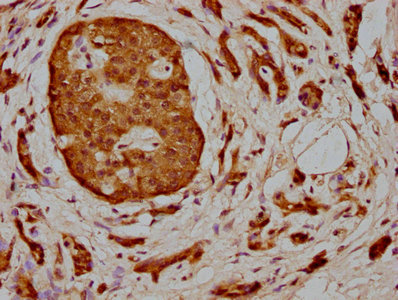

IHC image of CSB-PA013424LA01HU diluted at 1:400 and staining in paraffin-embedded human pancreatic cancer performed on a Leica BondTM system. After dewaxing and hydration, antigen retrieval was mediated by high pressure in a citrate buffer (pH 6.0). Section was blocked with 10% normal goat serum 30min at RT. Then primary antibody (1% BSA) was incubated at 4°C overnight. The primary is detected by a biotinylated secondary antibody and visualized using an HRP conjugated SP system.